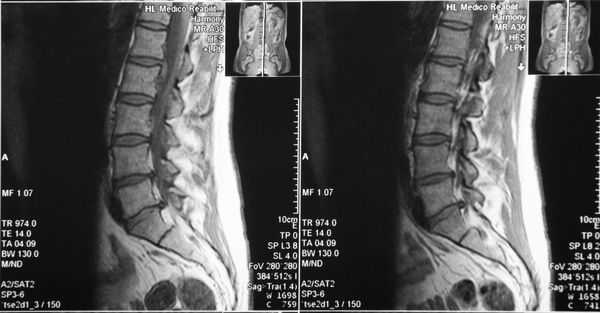

МРТ шейного отдела позвоночника: в Т2-режиме видны миелопатические очаги в сегменте С3-С6 на фоне абсолютного стеноза с уровня С3-С4 до С5-С6